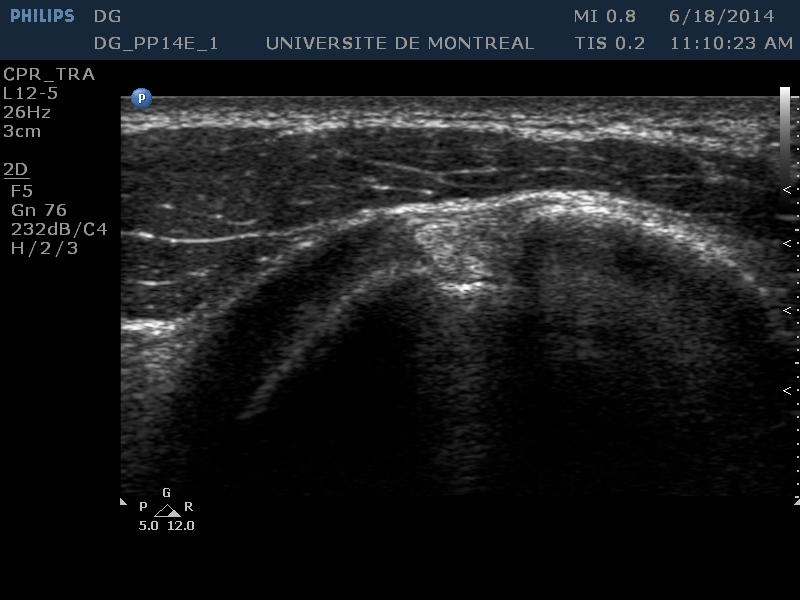

Transverse Plane

Objectives :

- Evaluation of the long biceps tendon

- Evaluation of the transverse humeral ligament

Suggested settings :

- Depth : 3-4 cm

- Gain : 70-75

- D/4/2

Probe position :

- Place the probe in transverse plane at the bicipital groove

Identifying structures (on the screen) :

| [D] | The deltoid appears at the top of the image |

|---|---|

| [LT] [GT] | The lesser tuberosity and greater tuberosity (circular hypoechoic zone of the humeral head) occupy the central portion of the screen respectively on the left and on the right of the image. |

| [THL] | The transverse humeral ligament (thin hypoechoic layer) forms the top part of the osteofibrous channel that is the bicipital groove. |

| [TLB] | The tendon of the long biceps is visible within the bicipital groove. |

| [SS] | The subscapular tendon is visible on the left of the image above the lesser tuberosity. |